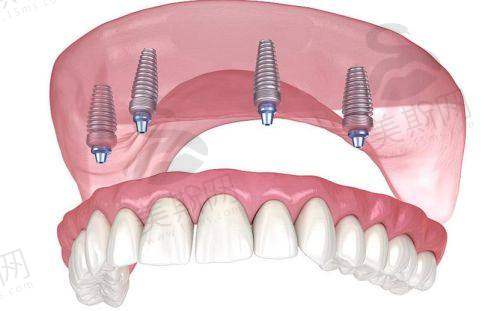

复杂种植:半口/全口ALL - ON - 4修复、牙槽骨植骨术、上颌窦提升术,高龄/糖尿病患者专属方案设计。

医院引进德国X - Guide动态导航种植技术,术前通过CBCT扫描构建三维口腔模型,术中实时引导种植体植入角度、深度,误差控制在0.1mm以内。针对半口/全口缺失患者,采用“即刻负重”技术,实现“当天种牙当天用”,较传统种植缩短3 - 6个月愈合周期。

实例2:全口ALL - ON - 4即刻种植(患者:张大爷,68岁)

“下半口牙掉光后吃饭都费劲,陈可医生推荐ALL - ON - 4技术,当天种完4颗植体就戴上了临时牙冠。现在3个月过去,啃苹果、吃肉都没问题,比活动假牙稳太多了!医院术后每个月都打电话提醒复查,护士还教我怎么清洁种植体,服务特别到位。”